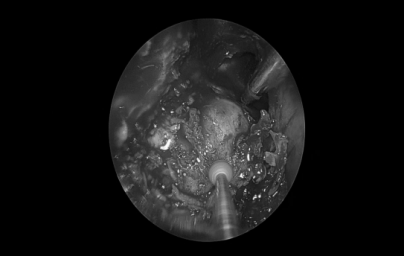

耳内镜检查:分泌性中耳炎(右)

电子喉镜检查:鼻息肉(双)

双耳鼓膜完整,右侧鼓膜内陷明显,右侧鼓室可见积液